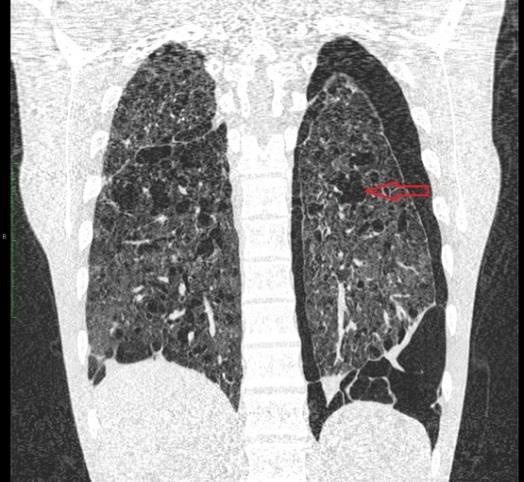

Mężczyzna lat 19 z nagłym nasileniem duszności. Od 2 lat postępująca duszność wysiłkowa, męczący suchy kaszel. Przy przyjęciu stan ogólny ciężki, duszność spoczynkowa, tachypnoe, tachykardia, SO2 89 % (tlenoterapia bierna 3l/min), szmer pęcherzykowy znacznie osłabiony nad lewym płucem i szczytem płuca prawego, opukowo odgłos bębenkowy nad płucem lewym. Dotychczas niezdiagnozowany. Od 13. r.ż palacz do 30 'skrętów z tytoniu' na dobę. W tomo- grafii klatki piersiowej wysokiej rozdzielczości obustronnie w płucach liczne różnokształtne przestrzenie cystyczne do 3 cm, dominujące w płatach górnych. W obu płatach guzki. Odma opłucnowa lewostronna. Wskaż najbardziej prawdopodobne rozpoznanie: